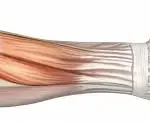

The hamstrings are a group of three essential muscles located at the back of the thigh: the biceps femoris, semitendinosus, and semimembranosus. These muscles work in coordination to facilitate critical movements such as bending the knee (knee flexion), extending the hip, and maintaining overall stability of the lower body. They are actively engaged in a wide range of physical activities, including running, jumping, cycling, and sports that require rapid changes in speed or direction, such as football, tennis, and sprinting.

Hamstring muscles overuse occurs when these muscles are repeatedly subjected to stress beyond their ability to fully recover. Unlike an acute hamstring strain or tear, which happens suddenly, overuse develops gradually over time due to continuous microtrauma and repetitive loading. This prolonged strain can result in symptoms such as muscle tightness, fatigue, reduced strength, imbalances between muscles, and even chronic discomfort that can affect both athletic performance and everyday activities. If left unaddressed, overuse may increase the risk of more severe injuries, including strains or tears.

While hamstring muscles overuse is often treated as a single overarching condition, it can present in different patterns depending on which specific hamstring muscle is predominantly affected. Understanding these variations is important because each muscle may respond differently to stress, and tailored treatment approaches are often required.